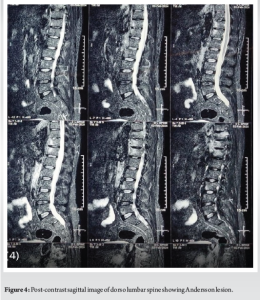

A 52-year-old man presented with a 20-year history of diffuse, non-radiating abdominal pain, localized to the right lower abdomen and aggravated by straining. He was diagnosed with a duodenal ulcer after an endoscopy and began treatment. He also reported 2 months of progressively worsening lower back pain, aggravated by walking and standing, without a history of trauma, tuberculosis, or constitutional symptoms. On examination, he had tenderness over the D11 region of the spine, with limited chest expansion and restricted, painful movements of the cervical and lumbar spine. Straight leg raise test and Faber’s tests were negative, with no motor or sensory deficits. HLA-B27 was positive, while the rheumatoid factor was negative. Radiographs showed loss of lumbar lordosis, with irregularities and erosions at the D11-D12 vertebral bodies (Fig. 1 and 2). Magnetic resonance imaging (MRI) revealed asymmetrical bilateral sacroiliitis, with paravertebral enhancement and syndesmophytes at D11-D12 and L2-L3. The Andersson lesion (AL) was hemispherical, hypointense on T1, and hyperintense on T2 and STIR images, with signs of reactive sclerosis and vertebral end plate erosions (Fig. 3-5). Right sacroiliitis with mild joint space reduction on the left side suggested chronic sacroiliitis. Based on these findings and the positive HLA-B27, a diagnosis of AS with AL was confirmed, with differential diagnoses including Pott’s spine, pyogenic infection, and malignancy.